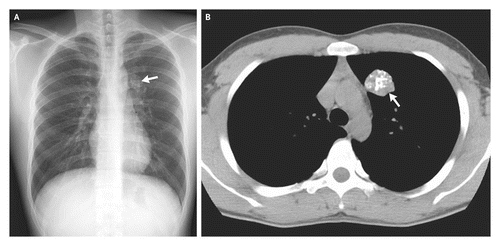

Целесообразна ли операция при моем диагнозе или возможно альтернативное лечение? Евгений Федорович. В августе 2017 года я прошла флюорографию, которая показала затемнение во втором сегменте легкого. Осмотра в мае 2017. Прошла лечение от пневмонии, последующий снимок показал наличие этого же затемнения без изменения. Результат прохождения первого РКТ 10 октября 2017г.:

Средостение расположено в типичном месте, в размерах не увеличено, с четкими контурами, обычной формы, без очаговых патологических образований.

В паренхиме S1-S2 сегментов верхней доли правого легкого определяются гетерогенные интертисциальные изменения за счет полиморфных очагов, размером от 8,5 мм до 44,1 мм в поперечнике, на фоне которых визуализируются участки уплотнения по типу матового стекла

В других сегментах паренхима без очаговых патологических образований, нормальной пневматизации. Архитектоника легочного и сосудистого рисунка легких без особенностей. Просвет трахеи и главных бронхов свободен, стенки без патологических изменений. Легочные синусы свободные, без патологических изменений. Легочные синусы свободные, без патологических изменений. Плевральные листки не утолщены.

Лимфоузлы переднего средостения (стернальные, преваскулярные и прекардиальные) не визуализируются. Лимфоузлы заднего средостения не увеличины. Лимфоузлы центрального средостения не увеличены.

Повторное РКТ 9 января 2018г. дало тот же результат, единственная разница в размерах: в первом случае от 8,5мм до 44,1мм. В поперечнике, во втором случае от9,6 мм до 44.4 мм в поперечнике.

Результат биопсии легкого от 17 октября: Опухолевидный стеноз В2верхнедолевого бронха справа III степени(полный) за счет обтурации просвета (с распадом).

Результат биопсии от 20 октября 2017 года: Уплотнение верхней доли правого легкого (ателектаз).

Опухолевидный стеноз (В2) верхнедолевого бронха справа III степени за счет обтурации просвета сдавления извне и инфильтрации слизистой оболочки (с распадом).

Результаты онкомаркеров отрицательные.